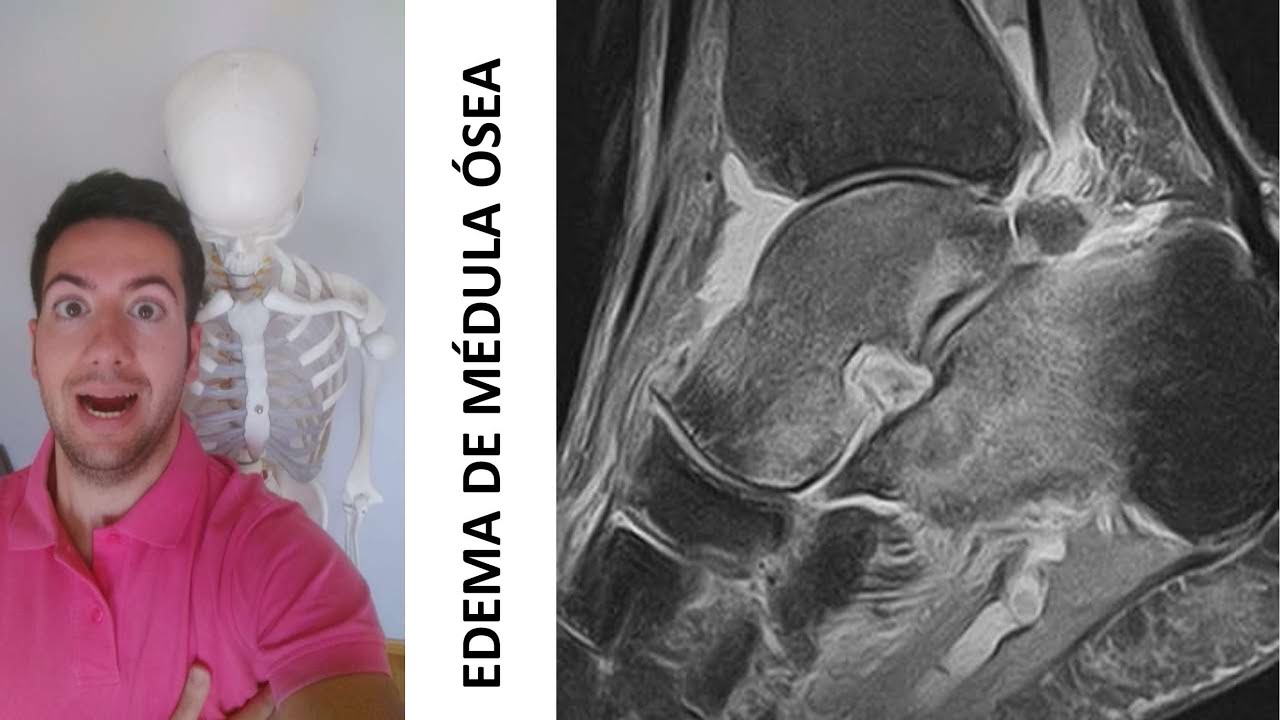

El edema medular suele diagnosticarse mediante una resonancia magnética (RM). La RM es una prueba de imagen que utiliza ondas de radio y un campo magnético para crear imágenes detalladas del interior del cuerpo.

Web¿Qué es un edema óseo? El edema óseo es una inflamación o lesión que ocurre en la zona medular del hueso, en el interior del hueso trabecular. Esta.

¿Conoces el edema de médula ósea? 🤔

Esta vez hablaremos sobre un reciente consenso de expertos sobre el edema de médula ósea doloroso basado en la evidencia científica. 🗣